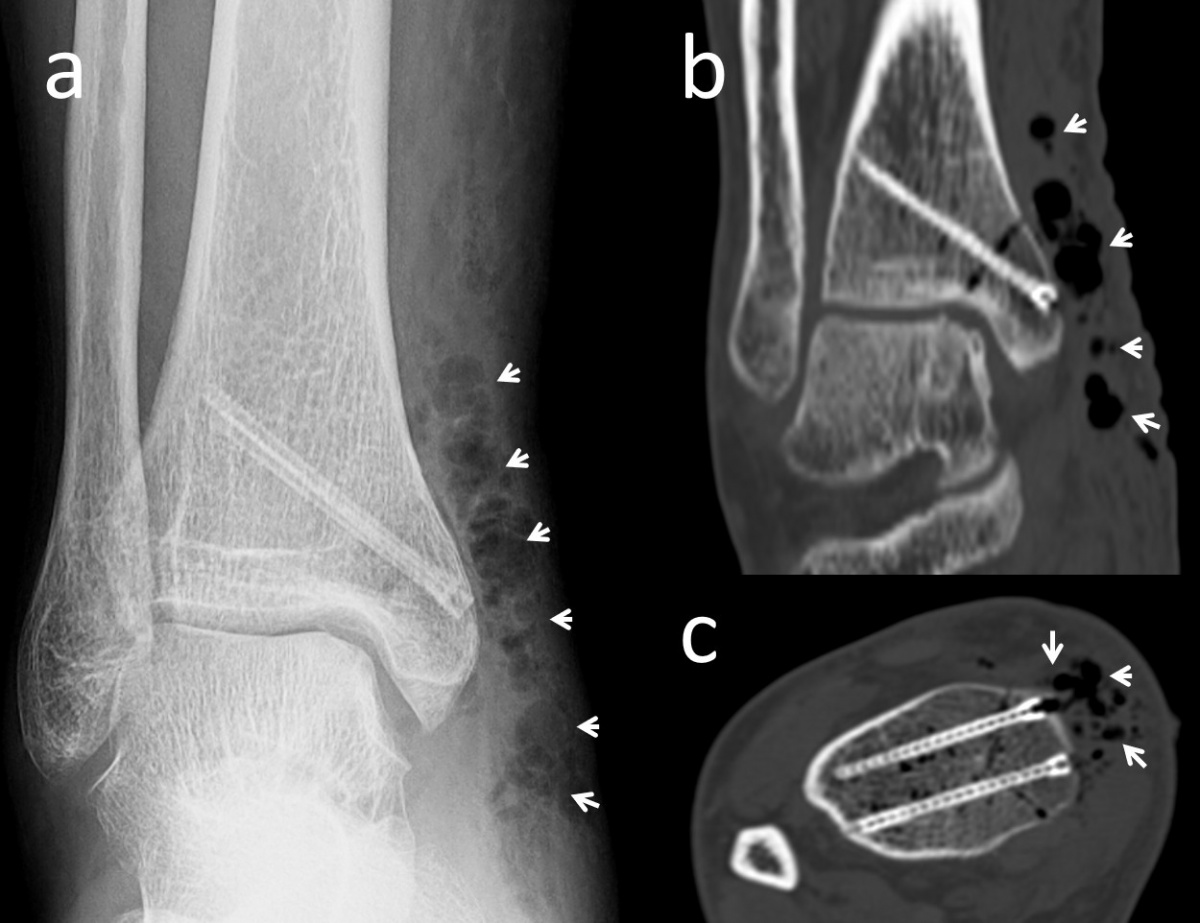

In Bezug auf die Gasbildung und Resorption zeigt die Computertomographie ähnliche Ergebnisse wie die konventionellen Röntgenaufnahmen. In der Frühphase sind sowohl die Schrauben als auch die umgebenden Gasansammlungen deutlich sichtbar (Abbildung 5). Langfristige CT-Untersuchungen zeigen, dass das Gas vollständig resorbiert wird und damit vollständig verschwindet. Die Schrauben sind bis zu ihrer Umwandlung in kortikales Knochengewebe deutlich erkennbar (Abbildung 6). Adil et al. haben nachgewiesen, dass diese Konturen vier Jahre nach der Implantation in der tomographischen Dichtemessung ähnliche Hounsfield-Einheiten aufweisen wie die umgebende Kortikalis (17). Darüber hinaus erzeugen Implantate auf Magnesiumbasis – im Gegensatz zu konventionellen Metallimplantaten wie Titanschrauben – nur minimale Metallartefakte (18-20). Für die Nachbeobachtung der Patienten stellt dies einen signifikanten Vorteil dar.

(schwarzer Pfeil) in der präoperativen lateralen Röntgenaufnahme des

Ellenbogens. (b) Röntgenaufnahme des Ellenbogens mit Gasansammlung

im Weichgewebe (weiße Pfeile) am ersten postoperativen Tag. (c)

Röntgenaufnahme des Ellenbogens 25 Tage nach der Operation, die

Gasmenge hat sich verringert (weißer Pfeil). (d) Bei der radiographischen

Nachbeobachtung nach 2 Monaten ist kein Gas im Weichgewebe

mehr sichtbar.

Läsion am Talus einer Innenknöchel-Osteotomie und Mosaikplastik

unterzogen wurde. Die biplanare Innenknöchel-Osteotomie

wurde mit zwei Magnesiumschrauben fixiert. (a) Die anterior-posteriore

Röntgenaufnahme des Knöchels am 7. postoperativen Tag zeigt an

der Operationsstelle diffuse Gasansammlungen im Weichgebe (weiße

Pfeile). (b) Koronare und (c) axiale CT-Aufnahmen mit sichtbarem Gas

(weiße Pfeile).